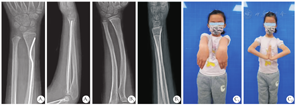

所有患儿均顺利完成手术,平均手术时间为33.9 min,范围在20.0~63.0 min;术中平均出血量为10.5 ml,范围在5.0~25.0 ml;平均透视次数为4.6次,范围在2~8次;切口平均长度为1.65 cm,范围在1.24~1.92 cm。所有患儿均获得解剖学或接近解剖学复位,均未发生医源性桡神经损伤,未发生浅表或深部感染。患儿平均随访时间为19.2个月,范围在6.0~31.0个月,骨折愈合满意后取出弹性髓内钉。随访中无患儿出现骨折再移位、畸形愈合、异位骨化及前臂旋转受限等,拇指背伸活动不受限,无拇长屈肌腱断裂。末次随访时Gartland和Werley腕关节评分为优20例,良1例,优良率为100%。所有患儿术后骨折正位对位率为(91.1±4.4)%,侧位对位率为(95.0±5.8)%,术后骨折正位成角为(2.8±1.2)°,侧位成角为(1.9±0.8)°。典型病例术后治疗结果见图4。

患儿全身麻醉,常规铅衣防护重要腺体,消毒铺巾后,取桡骨远端桡侧切口,长约1.5 cm,经C/G型臂X射线机透视确定桡骨远端骺板近端1~2 cm为进钉点,插入提前预弯的弹性髓内钉至骨折端0.5~1 cm。手法复位骨折,力求侧位骨折复位后对线良好,助手维持复位,保持肘关节伸直位。术者一手维持复位的骨折断端,一手握持手柄缓慢进钉,直至弹性髓内钉头侧预弯顶点通过骨折端且尾侧预弯顶点位于骨折线远端,此时透视可见骨折自然复位,后检查骨折端稳定性,确定骨折端弹性髓内钉把持良好,骨折端稳定(图2D)。剪断针尾,缝合,无菌敷料包扎,长臂石膏固定于肘关节屈曲90°、前臂旋转中立位。术后抬高患肢,4周去除石膏,行肘关节屈伸及前臂旋转功能锻炼。典型病例:患儿,女,7岁,经X线检查显示左侧桡骨远端MDJ骨折,术中操作见图3。